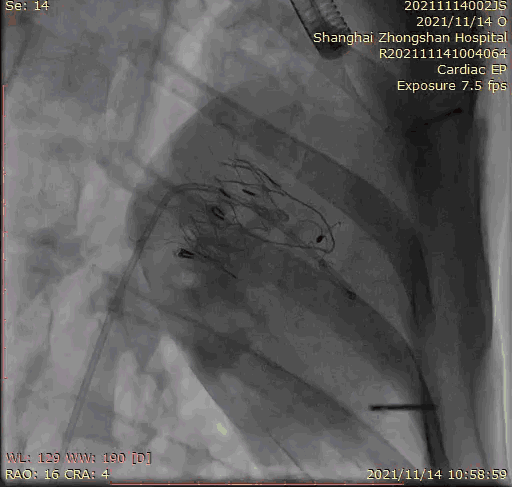

本次臨床前研究經右側頸靜脈置入LuX-Valve Plus輸送系統(tǒng)可調彎鞘管,在DSA及超聲引導下將人工三尖瓣瓣膜植入到原有三尖瓣位置,利用獨特的錨定技術將人工瓣膜支架可靠固定在預定的位置。

上海中山醫(yī)院葛均波院士、錢菊英院長、周達新教授、潘文志教授、潘翠珍教授、李偉教授共同完成此次臨床前研究。術后葛均波院士對Lux-Valve Plus的器械操作性能給予了高度評價,DSA和超聲影像也顯示出在本次研究中Lux-Valve Plus的安全性和有效性俱佳。